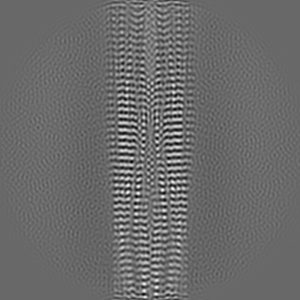

Tropomyosin-receptor kinase fused gene protein (TRK-fused gene protein; TFG) Low Complexity Domain (residues 237-327) P285L mutant, amyloid fiber

Helical reconstruction2.59 Å

Sample: amyloid fibril of protein TFG P285L

Fibril structures of TFG protein mutants validate the identification of TFG as a disease-related amyloid protein by the IMPAcT method.